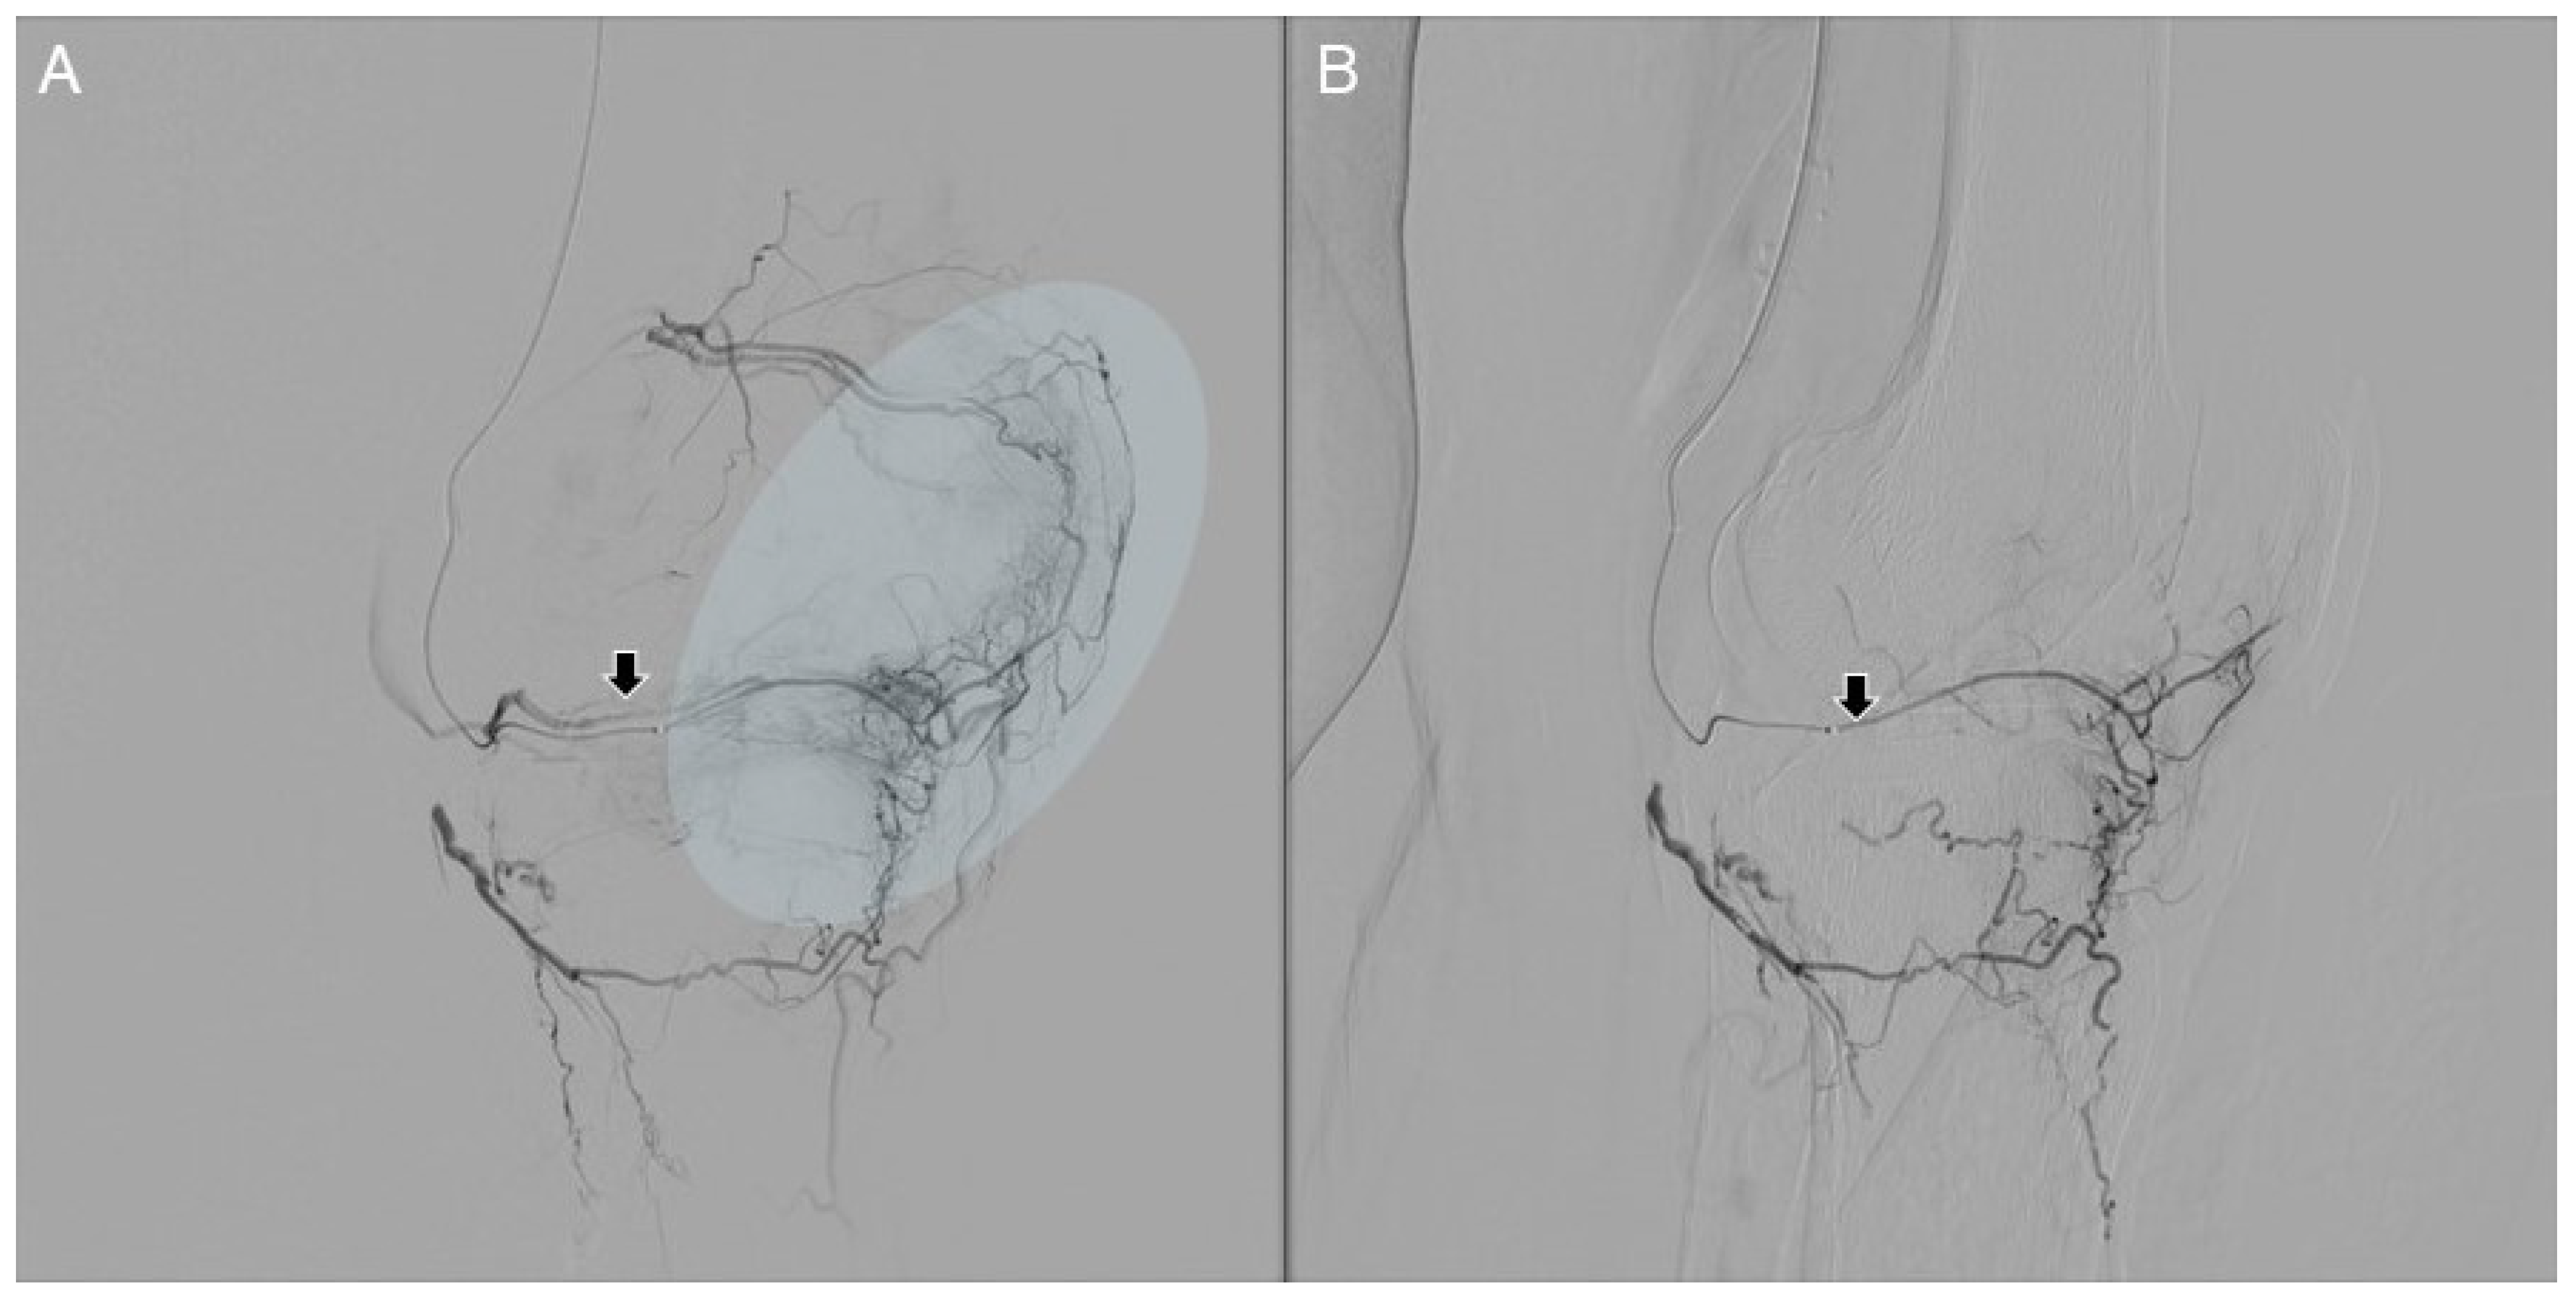

- Choi, J.W.; Ro, D.H.; Chae, H.D.; Kim, D.H.; Lee, M.; Hur, S.; Kim, H.-C.; Jae, H.J.; Chung, J.W. The Value of Preprocedural MR Imaging in Genicular Artery Embolization for Patients with Osteoarthritic Knee Pain. J. Vasc. Interv. Radiol. 2020, 31, 2043–2050. [Google Scholar] [CrossRef] [PubMed]

- Okuno, Y.; Korchi, A.M.; Shinjo, T.; Kato, S.; Kaneko, T. Midterm Clinical Outcomes and MR Imaging Changes after Transcatheter Arterial Embolization as a Treatment for Mild to Moderate Radiographic Knee Osteoarthritis Resistant to Conservative Treatment. J. Vasc. Interv. Radiol. 2017, 28, 995–1002. [Google Scholar] [CrossRef] [PubMed]

- Van Zadelhoff, T.A.; Okuno, Y.; Bos, P.K.; Bierma-Zeinstra, S.M.A.; Krestin, G.P.; Moelker, A.; Oei, E.H.G. Association between Baseline Osteoarthritic Features on MR Imaging and Clinical Outcome after Genicular Artery Embolization for Knee Osteoarthritis. J. Vasc. Interv. Radiol. 2021, 32, 497–503. [Google Scholar] [CrossRef] [PubMed]